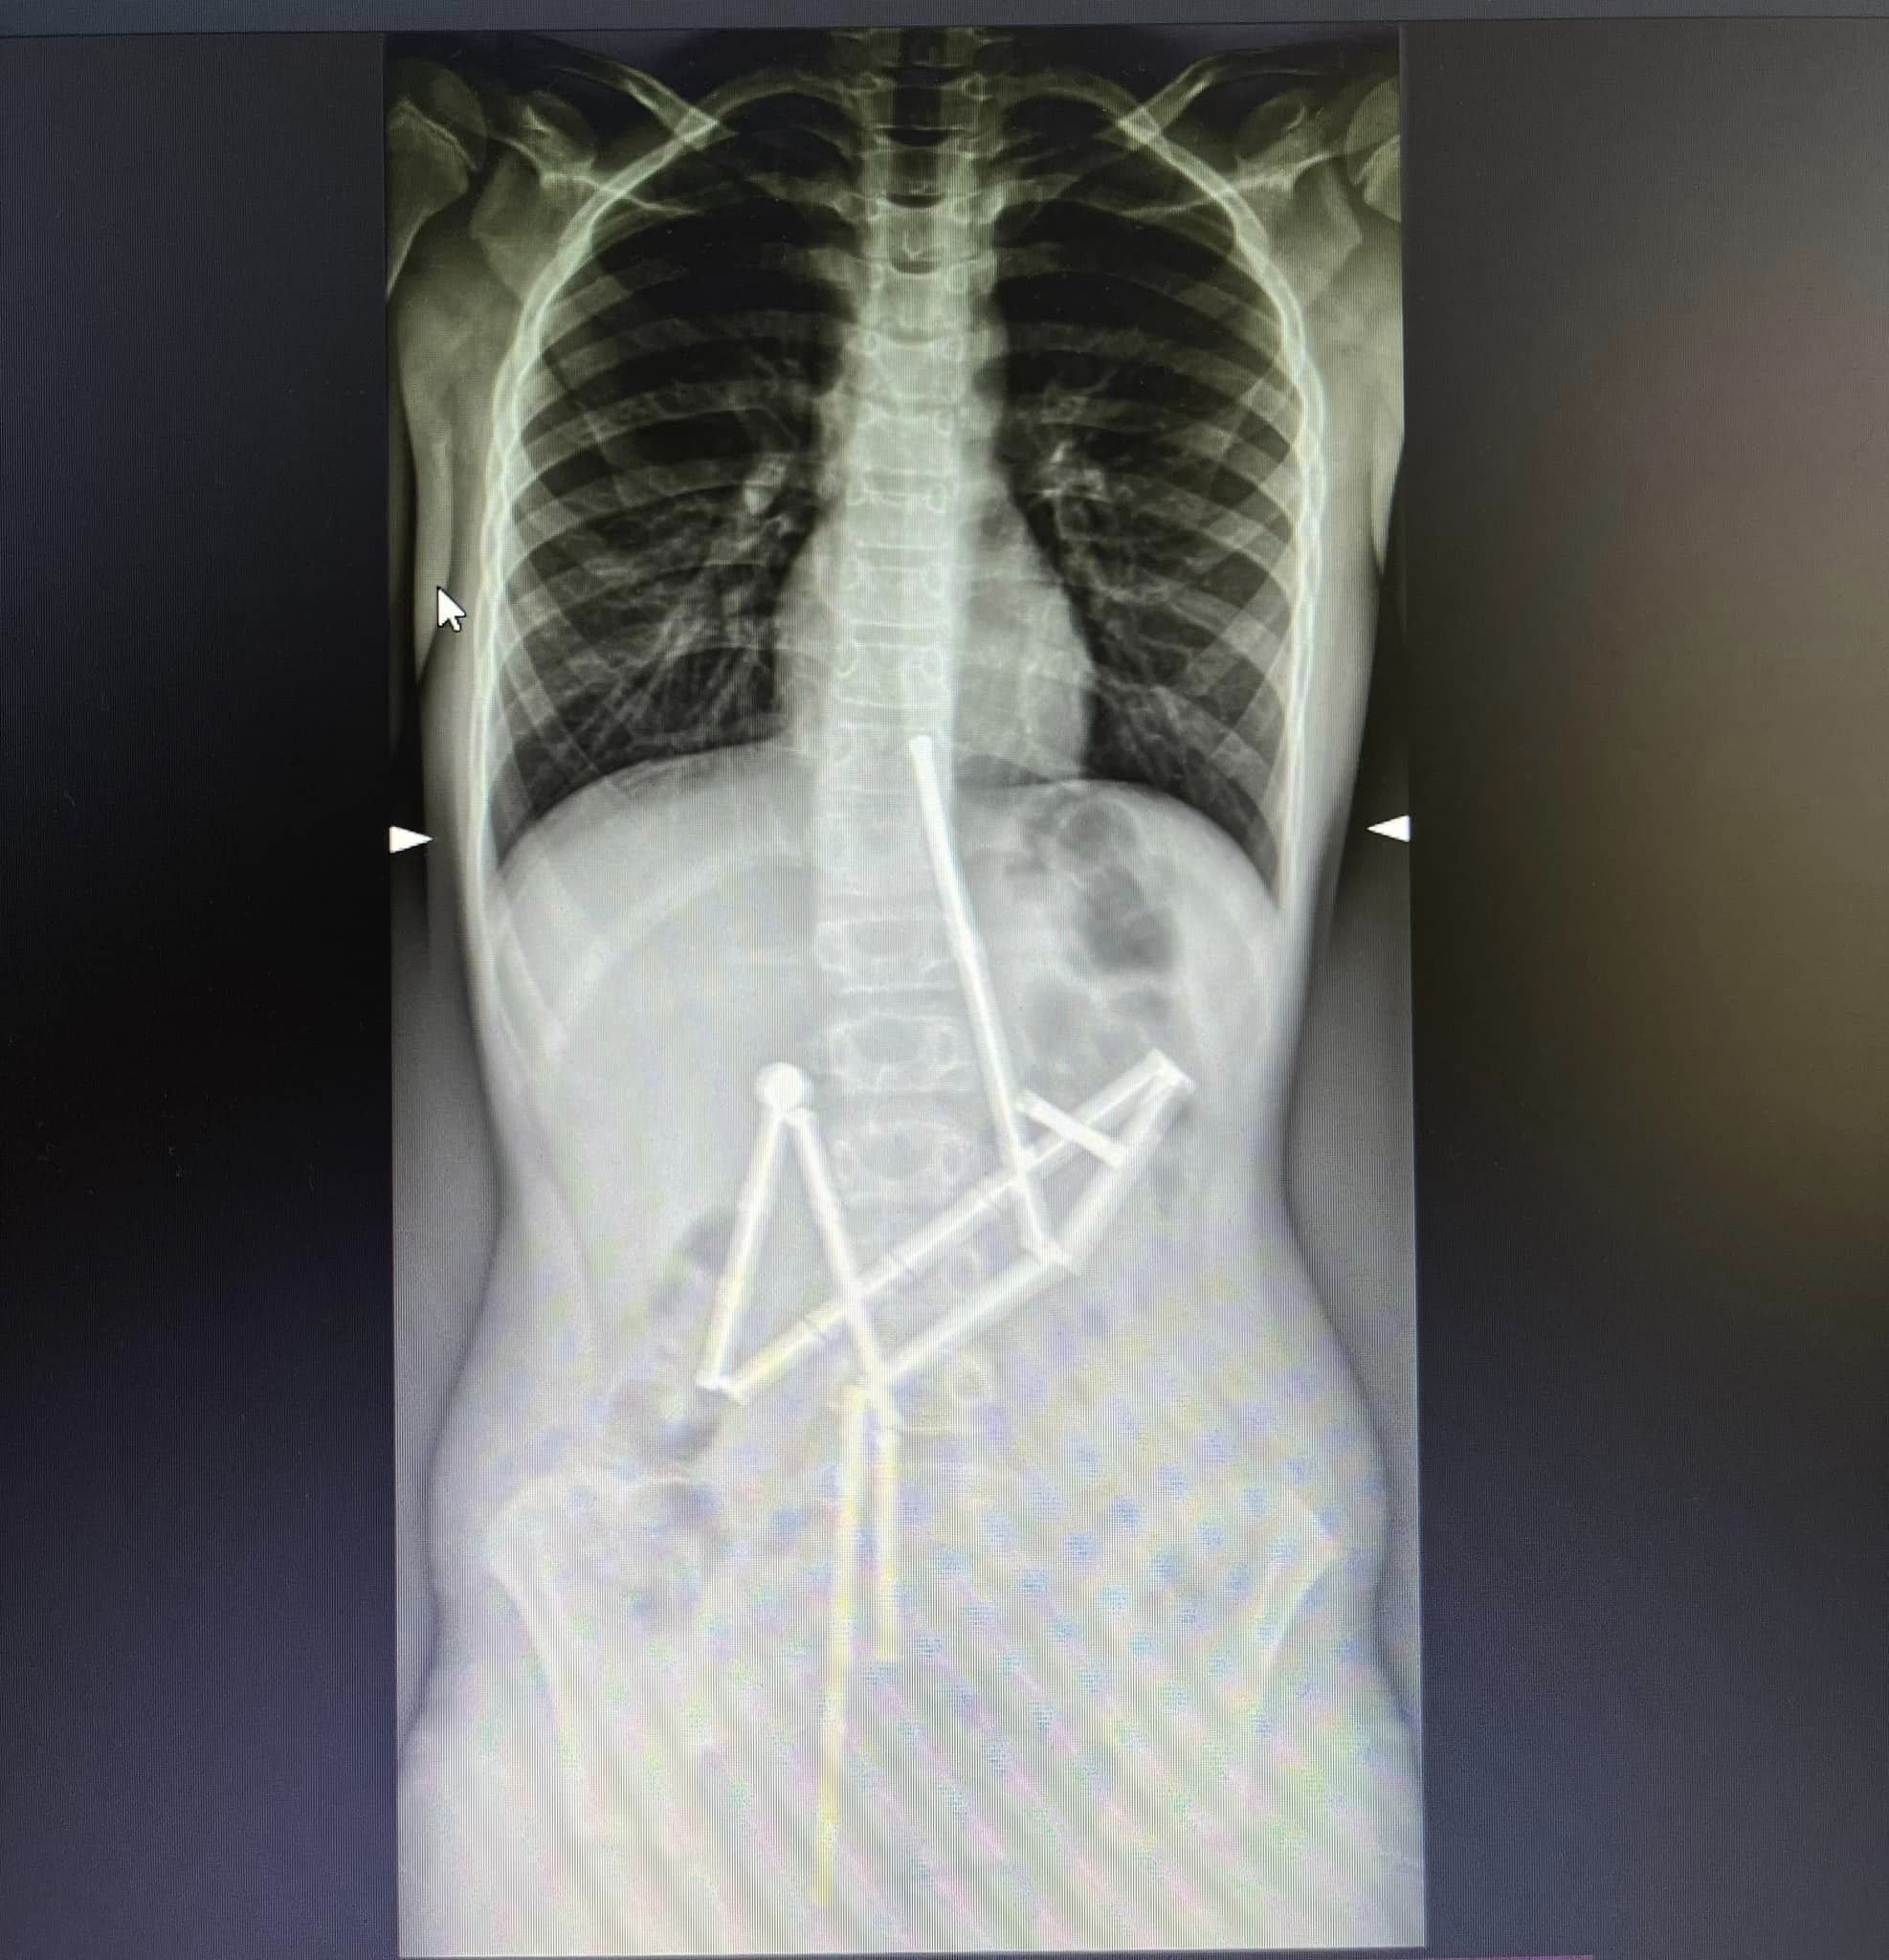

"<...> Уже на первом рентген-снимке специалисты увидели наличие в пищеварительном канале целой группы инородных тел, в которых удалось узнать магнитный конструктор. 20 магнитов находились в разных частях желудочно-кишечного тракта, и были соединены между собой. Консилиумом врачей было принято решение о проведении неотложного оперативного вмешательства", - сообщают в клинике.

"Отличие магнитов от других предметов, которые могут проглотить дети, заключается в их притягивании друг к другу и в ущемлении тканей. Как следствие, возникают зоны некроза (омертвения), перфорации полых органов, желудочно-кишечные непроходимости", - пояснили медики.